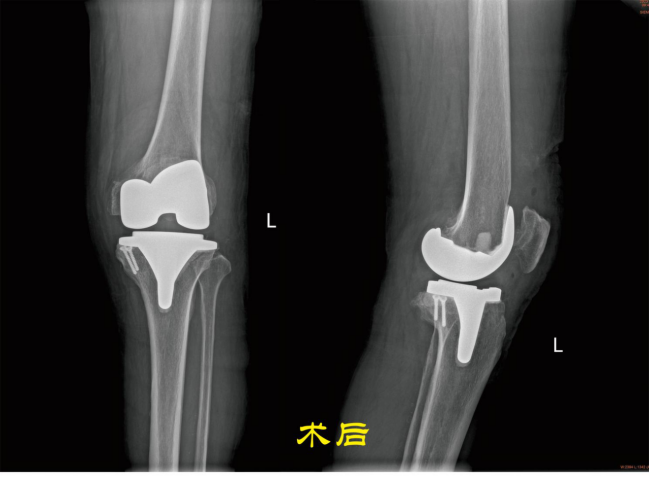

第三阶段治疗:如果患者膝关节病变集中在单侧,对侧关节里面软骨全层完整,膝关节内外侧副韧带及前后交叉韧带完好,则可行单髁置换术手术。 第四阶段治疗:膝关节内外侧关节软骨均损伤,比如类风湿性关节炎、强直性关节炎、膝关节的感染导致关节软骨破坏感染控制后等等,则需行全膝关节置换术。 (本图:左侧是截骨矫形内固定术后,右侧是全膝关节置换术后) 膝关节骨性关节炎阶梯治疗的有效路径及模式,可达到疾病有效治疗,保护有效劳动力,减少老年人因病致残生活不便引发的社会及家庭医疗负担。